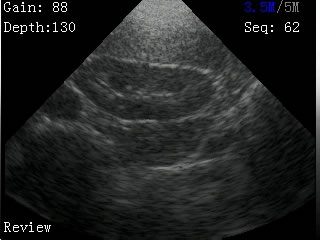

我司最新推出的V2型腕式B超,主机重量仅140克,看成目前全世界最轻的B超。

V2型腕式扇扫B超由主机、探头、外置电池、手握式键盘组成,重量只有140g(不含探头和电池)堪称全世界最轻的B超。

-扫描方式:机械扇扫

-探头频率:3.5MHz/5MHz双频率可变频探头

-扫描深度:≥180mm,70、110、130、150、192mm五档可调

-显示模式:B